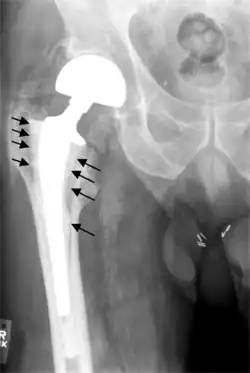

Hip prosthesis displaying aseptic loosening (arrows)

Hip prosthesis zones according to DeLee and Charnley,[43] and Gruen.[44] These are used to describe the location of for example areas of loosening.

On radiography, it is normal to see thin radiolucent areas of less than 2 mm around hip prosthesis components, or between a cement mantle and bone. These may indicate loosening of the prosthesis if they are new or changing, while areas greater than 2 mm may be harmless if they are stable.[45] The most important prognostic factors of cemented cups are absence of radiolucent lines in DeLee and Charnley zone I, as well as adequate cement mantle thickness.[46]